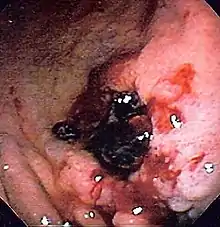

| Esophagogastroduodenoscopy images of gastritis with nodularity, erythema and spontaneous oozing, | |